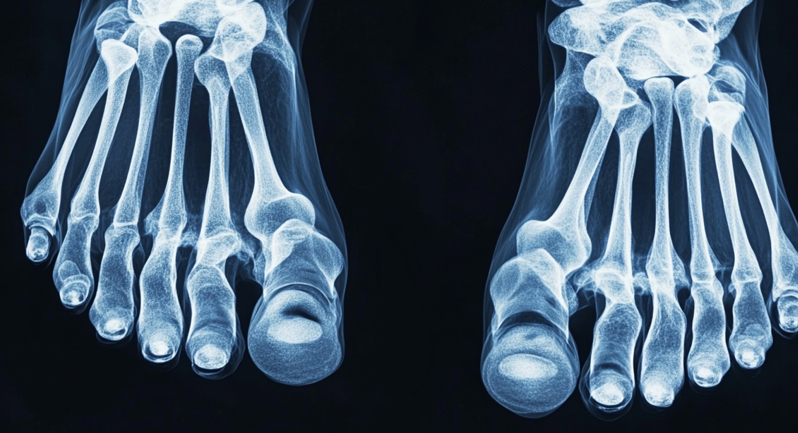

족저근막염은 발바닥 근막에 염증이 생겨 발생하는 통증을 말해요.

발뒤꿈치에서 시작해 발바닥 전체로 퍼지는 경우도 많아요

초기에 관리하지 않으면 발뒤꿈치 뼈가 자라거나 심한 경우 수술이 필요할 수도 있어요.